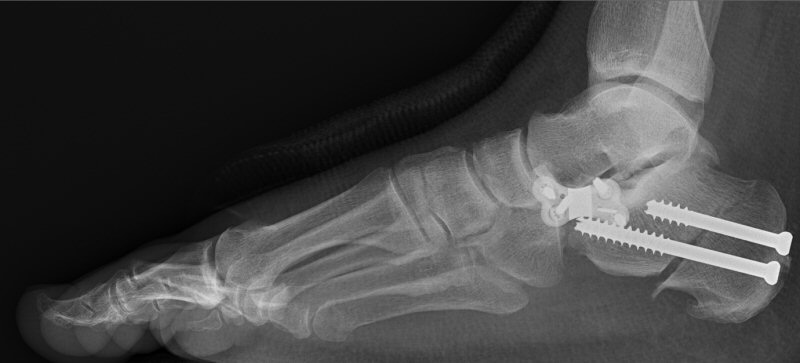

Flexibel plattfot:

• Medialiserande hälosteotomi. [1]

• Tibialis posterior (TP) inspekteras och eventuell tendinos åtgärdas. [1]

• FDL-transferering som förstärkning medialt. [1]

• Springligamentet bör inspekteras och vid behov åtgärdas. [1]

• Vid supinerad framfot trots ovanstående kirurgi kan man utföra TMT 1-artrodes eller plantarflekterande osteotomi (Cotton/Mt 1). [1]

• Vid kraftig abduktion av mellanfoten kan man överväga lateral förlängningsosteotomi enligt Evans. [1]

• Vid uttalad spetsfot (testat med hälen i neutralläge) kan man prova gastroknemiusförlängning (förlängning av hälsenan riskerar ge nedsatt kraft i frånskjutet). [1]